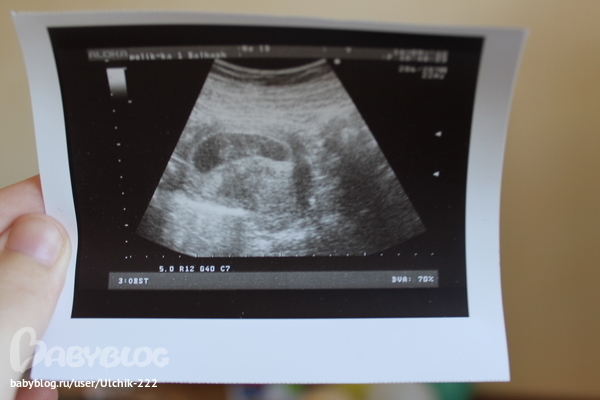

ВОТ ТАКИЕ МЫ!!!))))) Делюсь радостью)))

УЗИ, КТГ, доплерУтро началось прекрасно)))) смотрели с мужем на нашу ляку))))

А теперь подробности))))) плодное яйцо расположено в матке,средневнутренний диаметр 60 мм,соответствует 9 неделям, эмбрион ктр 23 мм, соответствует 9 неделям, сердцебиение +, желточный мешочек визуализируется, воротниковое пространство без особенностей,область придатков без особенностей,плодное яйцо по задней стенке матки,заключение: беременность 9 недель. Врач сказала, что срок по размерам плода поставила, т.е.от зачатия) а по акушерским у нас сегодня 9 недель 4 дня, а со дня О 7 недель 1 день))) вот такие мы большие)))) это так крутооо) в прошлый раз мы тоже опережали свой срок от зачатия) так же,как и в этот раз))) такая узистка хорошая,повернула нам с мужем монитор, все показала,рассказала подробно) показала сердечко))) так здорово бьется))) наша ляка такая милая)))))блииин)) не испытывала я таких ощущений никогда))) еле сдержалась,чтобы не разреветься)))) но лыба с лица не сходила))) муж замер)))) классное утро)))) всех целую,всех люблю))) анализы сдавали в 6 недель после овуляции- хгч 123071,прогестерон -24.01...прогестерон это пипец конечно(((( был 37 на 5 неделе( ну что начала дюф пить по 2 табл.в день, и утрожестан 200 на ночь вагинально...сегодня БТ поднялась на градус,посмотрим,что завтра будет) а так ничего не беспокоит,ттт)) от этого прогика и на узи в ускоренном порядке побежали.)))) врач сказала,что отлично,а прогик может быть моей индивидуальной особенностью...ну посмотрим))) через недельку буду в краснодаре,пойду на учет вставать, че они мне там скажут по этому поводу)) я сама знаю девочки ,что прогик низкий,но вот ничего же не беспокоит меня и малыш развивается отлично))) с динамикой) уже была в трех разных клиниках,и говорят все что нормально все...но я вот все равно решила дюф пить...хуже не будет от него как мне кажется)))